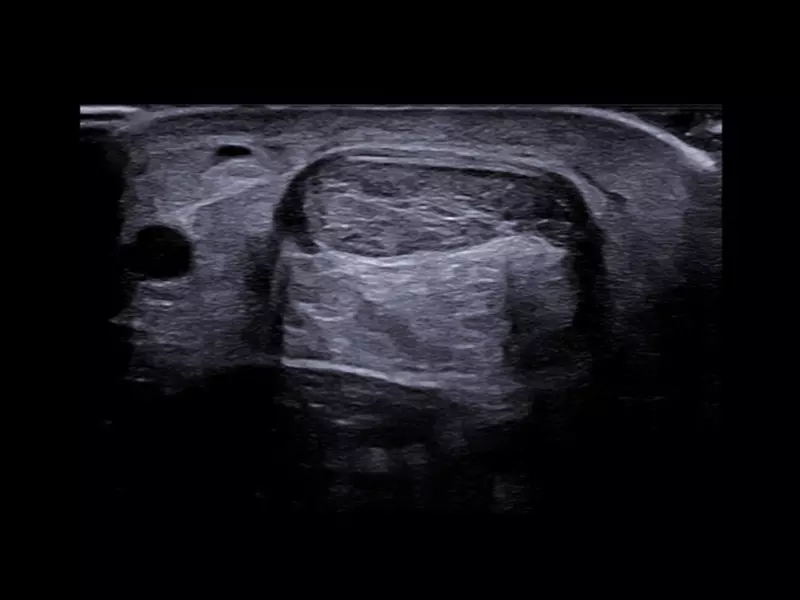

MyLab™9 Platform - High resolution imaging in testis

MyLab™9 Platform - High resolution imaging in testis